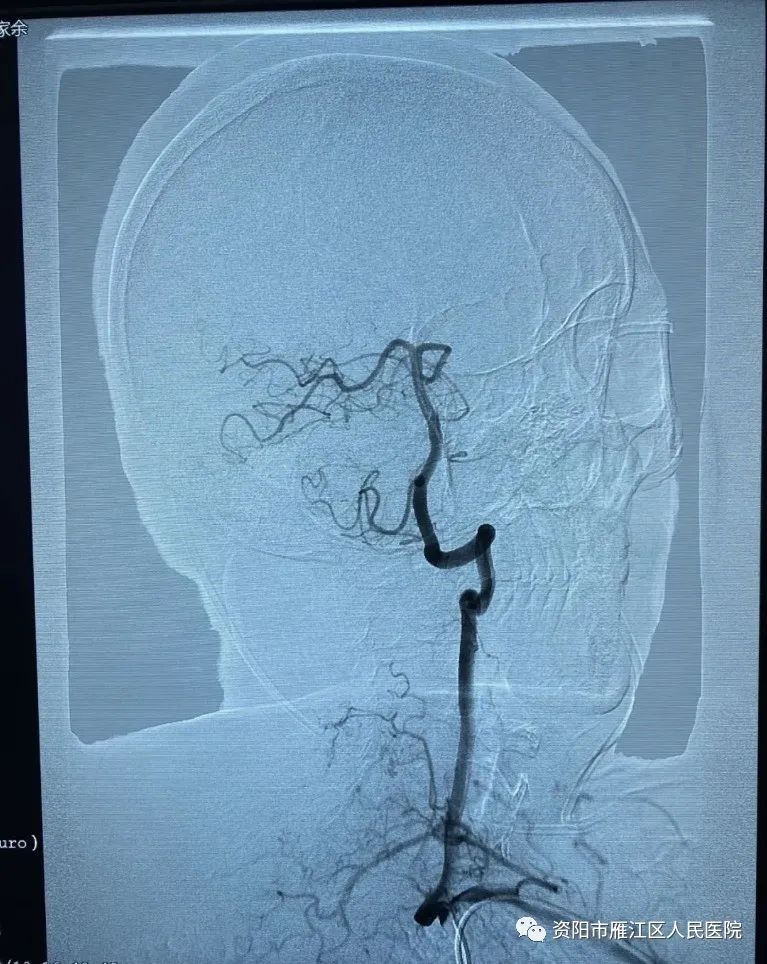

经桡动脉穿刺是目前冠脉介入(包括急诊介入治疗)的优先选择,目前已是冠脉介入治疗指南的I类推荐,此项技术不仅能明确脑管血管病变情况,同时还能为治疗方案提供了准确的信息。患者术后即可下床活动,满意度及舒适度得到了提高了,真正体现了微创、快速、准确的救治理念。但是脑血管较之冠状动脉解剖复杂,血管变异及迂曲多,经桡动脉全脑血管造影对神经介入医生手术技术有较高要求。

本着优质服务理念,为了让广大患者享受到更加优质方便快捷的诊疗服务,资阳市雁江区人民医院神经内科始终坚持以病患为中心,勇于攀登,不断求新,自2022年3月开始,在院领导,科主任带领下,在雁江区率先开展经桡动脉入路全脑动脉造影术,至2022年10月,累计完成全脑血管造影160余例。手术效果满意,术后病人即可下床活动,卧床时间短,极大地减轻了患者术后的痛苦,缩短了患者的住院时间,获得广大病人及家属一致好评,为广大患者提供了更优质的医疗技术服务。